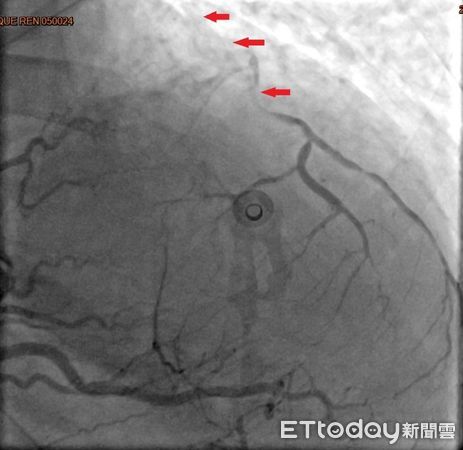

▲38歲的林小姐冠狀動脈嚴重阻塞。(圖/台北慈濟醫院提供,下同)

38歲的林小姐是追星族,雖有高血脂及心臟病家族史但平時身體無恙,去年冬天前往演唱會途中,於捷運站內突然喪失意識,站內人員立即協助施行CPR,隨後EMT前往接手急救與電擊,並立即送往急診,一連串急救處置後,經心導管檢查確認為急性心肌梗塞,且三條冠狀動脈都已嚴重阻塞。

台北慈濟醫院心臟血管外科宋鎮宇醫師指出,由於患者三條冠狀動脈嚴重阻塞,其中最主要的左前降支近端更呈現完全阻塞狀,已無法透過氣球擴張或支架方式處理,考慮患者年紀尚輕,緊急實施冠狀動脈繞道手術,免於因持續灌流不足引發的惡性心律不整、心臟衰竭等併發症,術後經歷拔管、病房積極的心肺復健,於兩週後返家。後續門診持續藥物治療。